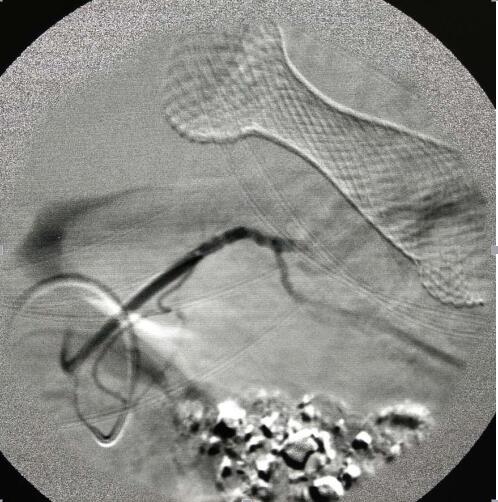

栓塞完成后再次造影

提示肿瘤供血动脉分支明显减少,大部血流中断